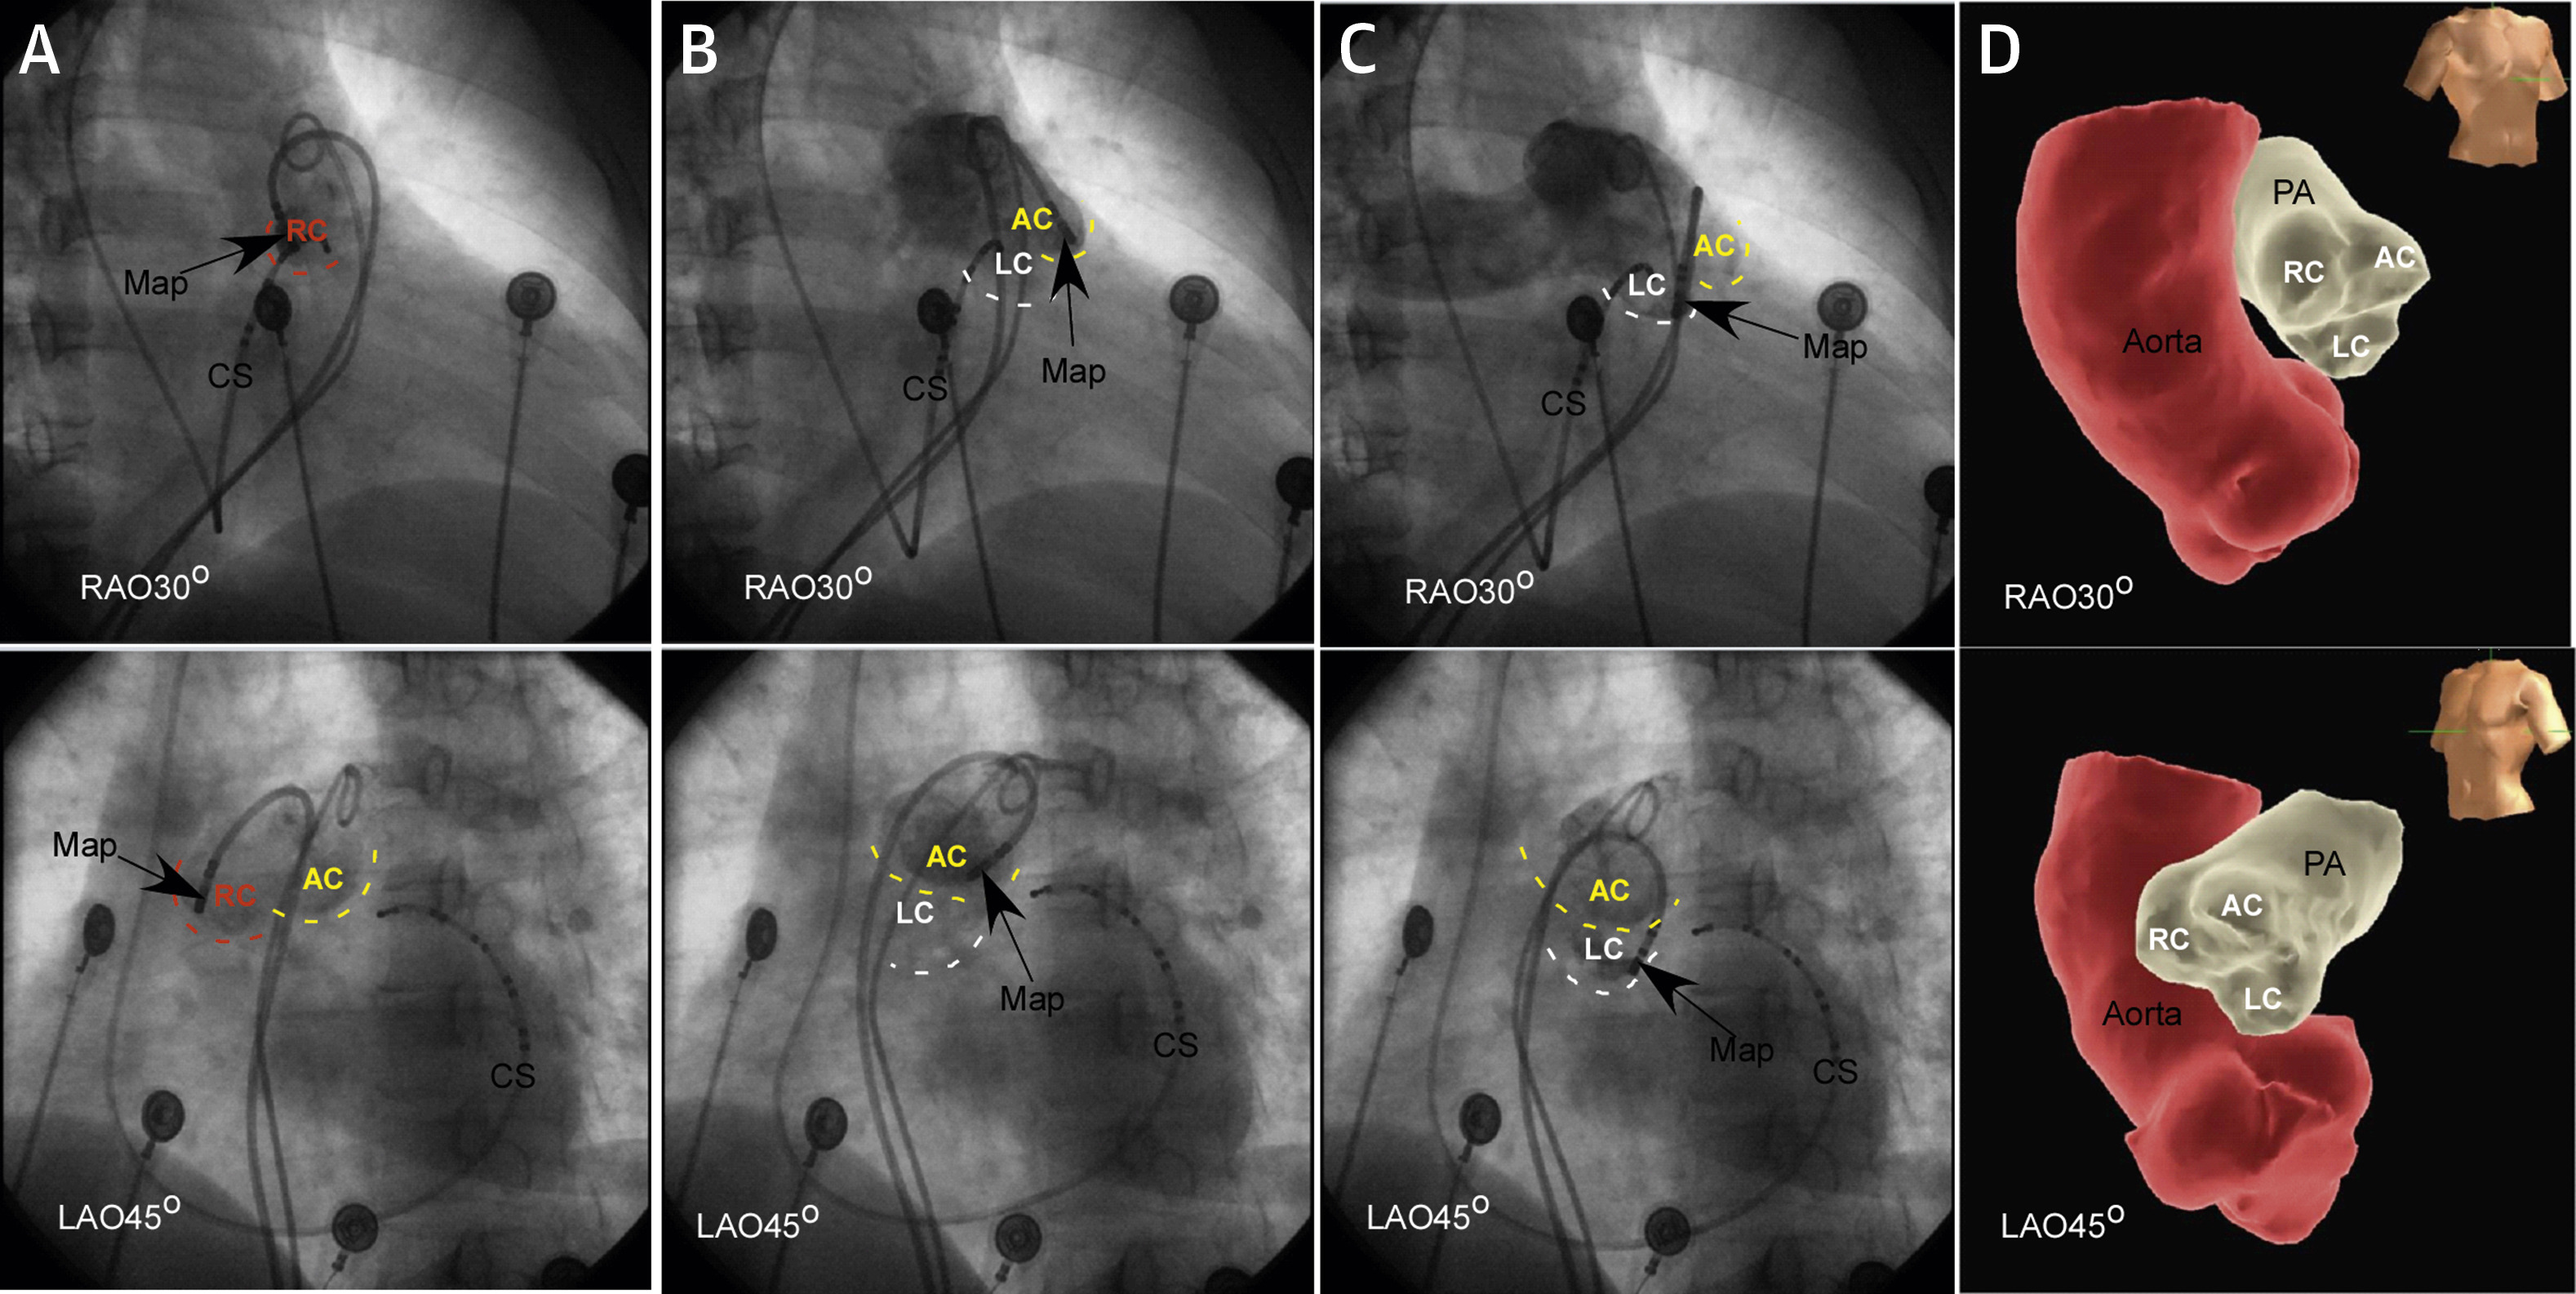

Ablation in coronary cusps - Aware of relationship to coronaries

cor_angio.jpg

Pulmonary sinus cusp VT

pulm_cusp.jpg

Liao Z, Zhan X, Wu S, Xue Y, Fang X, Liao H, et al. Idiopathic ventricular arrhythmias originating from the pulmonary sinus cusp: Prevalence, electrocardiographic/electrophysiological characteristics, and catheter ablation. J Am Coll Cardiol 2015; 66: 2633–2644.

Suspect when unsuccessful in high RVOT

psc_site.jpg